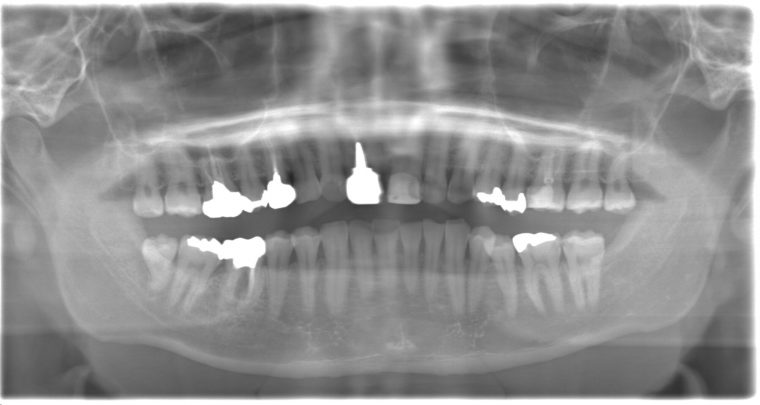

CASE 13

| 年齢・性別 | 32歳・男性 |

| 主訴 | 左上下の奥歯が痛い |

| 抜歯期間 | 60分 |

| 抜歯費用 | 約6,000円 別途CT撮影で3,000円 (2022年8月現在) |

| 抜歯内容 | 左上下の親知らず、左下7抜歯 |

| 治療方針 |

初診時は左上下の痛みでご来院されました。全体的に歯石を除去した後、主訴の解決のために虫歯が進行している左上下の親知らずと左下7の抜歯を行いました。 歯石除去と抜歯を行った後は、痛みが引いてきて口腔内の環境が変わったことに喜んでくれました。 今後は歯ぐきの状態を良くしながら、虫歯や欠損部の治療を行っていきます。 |